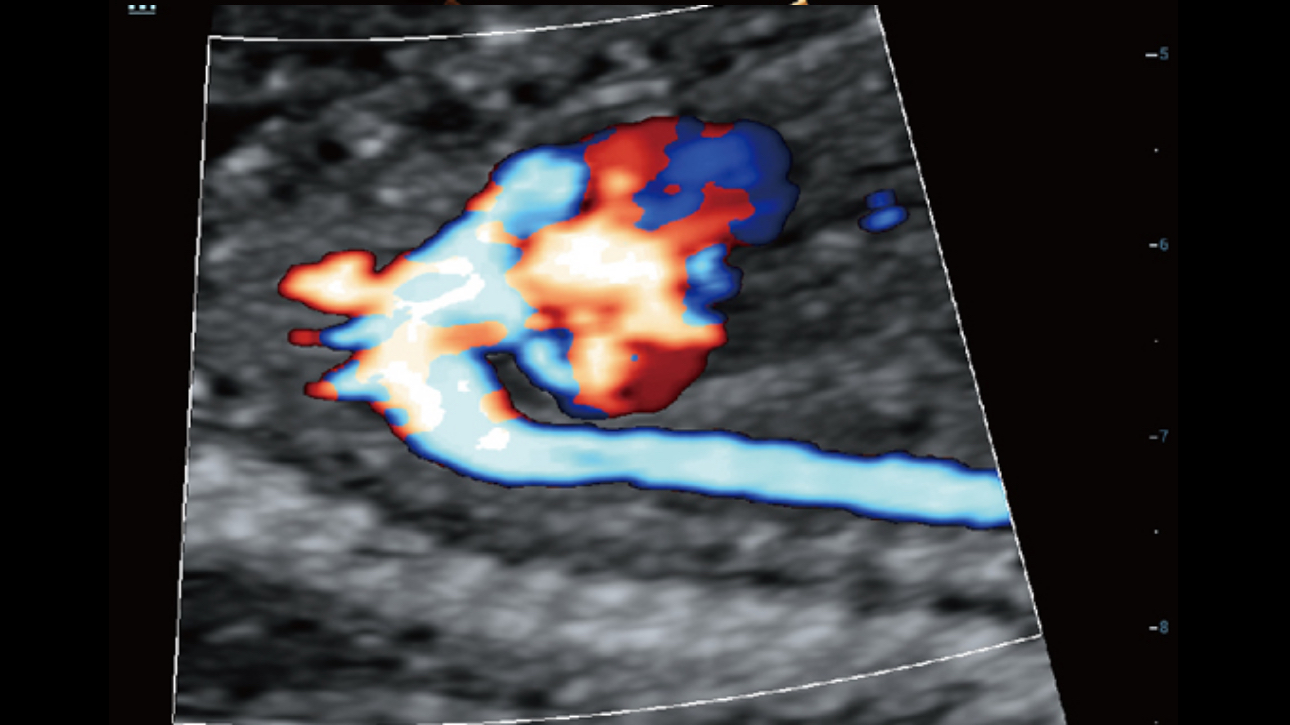

The channel data based ZST+ is an extraordinary innovation, representing an ultrasound evolution. Transforming ultrasound metrics from conventional beamforming to channel data based processing; ZST+ is able to deliver multiple imaging advances: Advanced Acoustic Acquisition, Dynamic Pixel Focusing, Sound Speed Compensation, Enhanced Channel Data Processing and Total Recall Imaging.

Dynamic Pixel Focusing technology allows the Resona 6 to achieve extreme uniformity in pixel level throughout the whole field of view. Now there's no need to adjust the focal positions to achieve uniformity across patient exams.

Channel data based ZST+ provides Enhanced Channel Data Processing for greatly improved imaging clarity. By multiple and retrospective channel data processing, it makes the best use of acoustic information for image improvement.

HD Scope: By processing channel data retrospectively, HD Scope enables tissue-specific enhancement with improved detailed information and image contrast on specific region of interest.